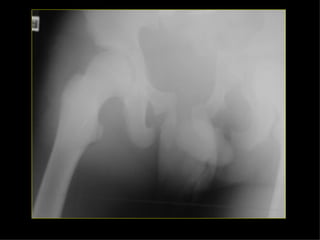

HOMBRO BRAZO CODO ANTEBRAZO MUÑECA MANO Monteggia Colles Fx escafoides

HOMBRO BRAZO CODOANTEBRAZO MUÑECA MANO Monteggia Colles Fx escafoides

ESTABLES INESTABLES FxMalgaigne En libro abierto En asa de cubo En horcajadas Fx por avulsión Del ala iliaca Del sacro Fx aisladas de las ramas pélvicas

CADERA FEMUR RODILLAPIERNA TOBILLO PIE Eversión Inversión